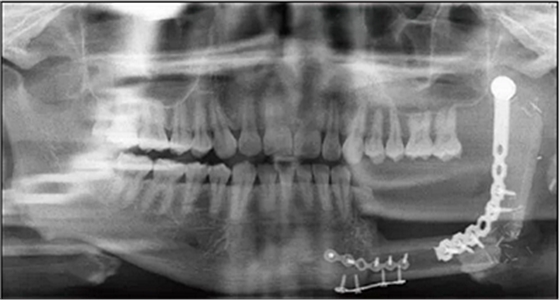

2014年6月9日于本院行下頜骨左側(cè)成釉細(xì)胞瘤切除術(shù)+下頜骨節(jié)段性切除術(shù)+重建板重建術(shù)+血管化腓骨肌皮瓣轉(zhuǎn)移修復(fù)術(shù)+鈦板內(nèi)固定術(shù)+血管吻合術(shù)+牽引釘植入術(shù)+拔牙術(shù)(圖2)。

2016年3月22日復(fù)查,全景片示34~37牙缺失,左下頜單層腓骨移植,腓骨與下頜骨對(duì)接處骨愈合良好,鈦板鈦釘在位(圖3)。

并于左側(cè)腓骨移植區(qū)植入4顆Nobel Active 4.3 mm×11.5 mm種植體+RP 4.5 mm復(fù)合基臺(tái)(型號(hào)36626)(圖5)。

種植體植入后拍攝錐形束CT(cone-beam computed tomography,CBCT)顯示種植體在位,復(fù)合基臺(tái)對(duì)接在位,骨愈合良好(圖6)。